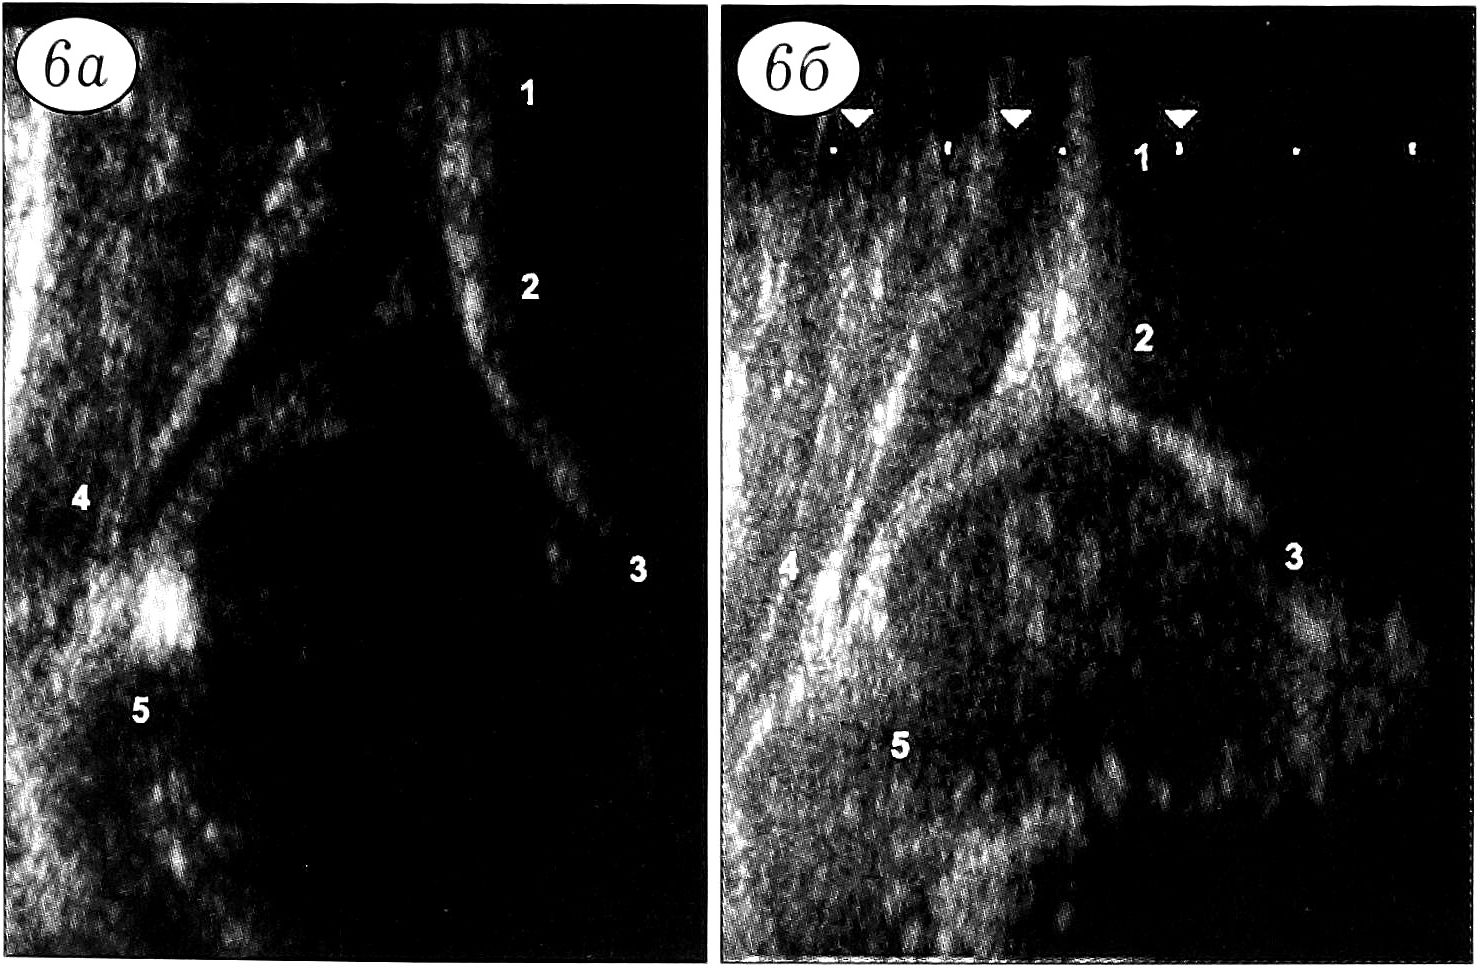

У 29 новорожденных, отнесенных к 3-й группе, ППГКК был ниже, чем в целом для всех обследованных (р<0,001). В возрасте 4-5 мес он повышался до нормального уровня. Исключение составили 4 ребенка. У одного из них ППГКК при рождении равнялся 39, в 2-месячном возрасте — 41, а в 5 мес определить его было невозможно, поскольку теневая дорожка ядра окостенения перекрывала нижний край ацетабулярной крыши. Расстояние k у этого ребенка составляло 7 мм, что превышало нормальную величину и указывало на подвывих головки бедра, который был подтвержден рентгенологически (рис. 7). У 3 других девочек с ультрасонографическими признаками дисплазии тазобедренных суставов рентгенологическая картина была нормальной и при ультразвуковом исследовании в 2 и 4-5 мес констатировано нормальное состояние тазобедренных суставов. Лечение им не проводилось.

Рис. 7. Ультрасонограммы (а, б) и рентгенограмма (в) тазобедренных суставов больной 3-й группы. а — при рождении головка правого бедра не полностью покрыта ацетабулярной крышей; б — к 5 мес головка правого бедра сублюксирована в латеральную сторону (стрелкой показан центр окостенения); в — подвывих подтвержден рентгенологически.